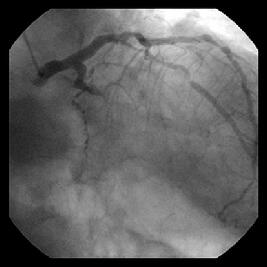

(特に急性期)であることを考えCB3.0×10mmで終わりました。(割れてますが・・

退院前の確認カテでもflow, lumenは確保されていました。(割れてましたが・・

Fig.はpreの造影と、Thrombuster後のIVUS、post CBの造影です。